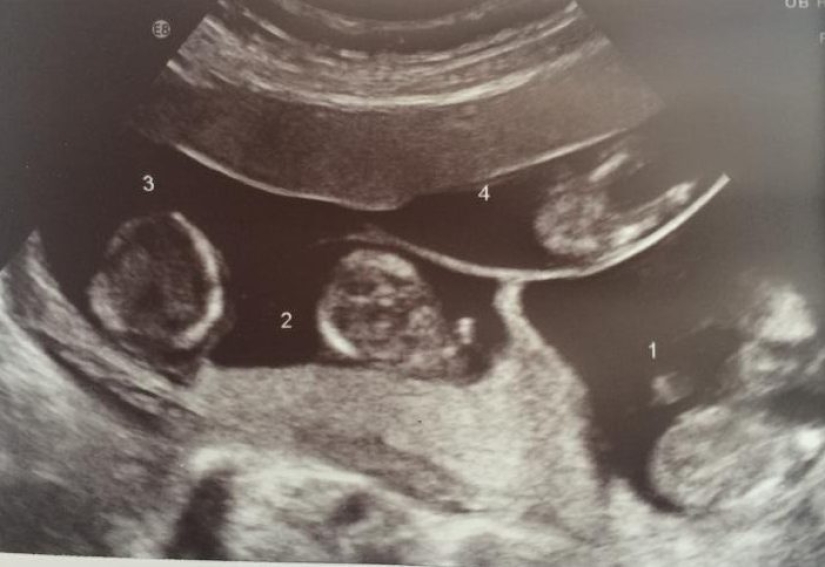

La mujer no pudo quedar embarazada durante mucho tiempo debido a problemas de salud, pero en 2014 la prueba mostró un resultado positivo muy esperado. ¿Cuál fue la sorpresa de los padres y médicos recién acuñados cuando se descubrió que no esperaban un hijo, sino cuatro a la vez?

Los cuatrillizos concebidos sin inseminación artificial nacen una vez cada 700.000. En el Reino Unido, este caso es único. Katelina concibió cuatro mellizos al mismo tiempo, que no son similares entre sí. Ahora los niños ya han cumplido 4 años.

Las primeras experiencias se asociaron con el curso normal de un embarazo tan complejo. Los médicos aconsejaron inicialmente a la mujer que dejara solo dos fetos, ya que existía el riesgo de perderlos todos y una amenaza para la salud de la madre. Pero, Katelina decidió dejar todo como está.

Katelina ingresó en el hospital para su preservación en enero de 2015, a las 27 semanas de embarazo. Los cuatrillizos nacieron por cesárea en febrero, a la semana 30 de embarazo.

Sofía pesaba 1,637 kg, Romano — 1,276 kg, Eston - 1,417 kg, y Amelia - 1,559 kg. Todos los bebés nacieron sanos.